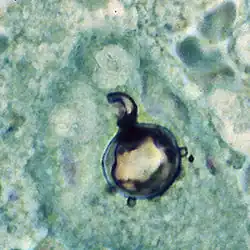

Paracoccidioides brasiliensis is a dimorphic fungus and one of the two species that cause paracoccidioidomycosis (the other being Paracoccidioides lutzii).[1][2][3][4] The fungus has been affiliated with the family Ajellomycetaceae (division Ascomycota) although a sexual state or teleomorph has not yet been found.[5]

Paracoccidioides brasiliensis is a nonphotosynthetic eukaryote with a rigid cell wall and organelles very similar to those of higher eukaryotes.[3][8] Being a dimorphic fungus, it has the ability to grow an oval yeast-like form at 37 °C and an elongated mycelial form produced at room temperature.[9] The mycelial and yeast phases differ in their morphology, biochemistry, and ultrastructure.[8] The yeast form contains large amounts of α-(1,3)-linked glucan.[10][11] The chitin content of the mycelial form is greater than that of the yeast form, but the lipid content of both phases is comparable.[10]

The yeast reproduces by asexual budding, where daughter cells are borne asynchronously at multiple, random positions across the cell surface. Buds begin by layers of cell wall increasing in optical density at a point that eventually gives rise to the daughter cell.[3] Once the bud has expanded, a cleavage plane develops between the nascent cell and the mother cell. Following dehiscence, the bud scar disappears.[8] In tissue, budding occurs inside the granulomatous center of the disease lesion, as visualized by hematoxylin and eosin (H&E) staining of histologic sections.[10] Nonbudding cells measure 5–15 μm in diameter, whereas those with multiple spherical buds measure from 10–20 μm in diameter.[10] In electron microscopy, cells with multiple buds have been found to have peripherally located nuclei and cytoplasm surrounding a large central vacuole.[12] In the tissue form of P. brasiliensis, yeast cells are larger with thinner walls and a narrower bud base than those of the related dimorphic fungus, Blastomyces dermatitidis.[10] The yeast-like form of P. brasiliensis contains multiple nuclei, a porous two-layered nuclear membrane, and a thick cell wall rich in fibers, whereas the mycelial phase has thinner cell walls with a thin, electron-dense outer layer.[8]

Paracoccidioides brasiliensis causes mucous membrane ulceration of the mouth and nose with spread through the lymphatic system. A hypothesized portal of entry for the fungus to the body is through the periodontal membrane.[30][31] The route of infection is assumed to be inhalation following which the infective propagule gives rise to the distinctive multipolar budding yeast forms in the lung resembling a "ship's wheel" seen in histological sections.[9][32] Both immunologically normal and compromised people are at risk for infection.[9] The lungs, lymph nodes, and mucous membrane of the mouth are the most frequently infected tissues.[10] The pathological features of paracoccidioidomycosis are similar to those seen in coccidioidomycosis and blastomycosis.[33] However, in the former, the lesions first appear in the lymphoid tissue and then extend to mucous membranes,[33] producing localized to diffusive tissue necrosis of the lymph nodes.[33] The typically extensive involvement of lymphoid tissue and the limited occurrence of the gastrointestinal tract, bone and prostate set the clinical picture of paracoccidioidomycosis apart from that of blastomycosis.[10][33]